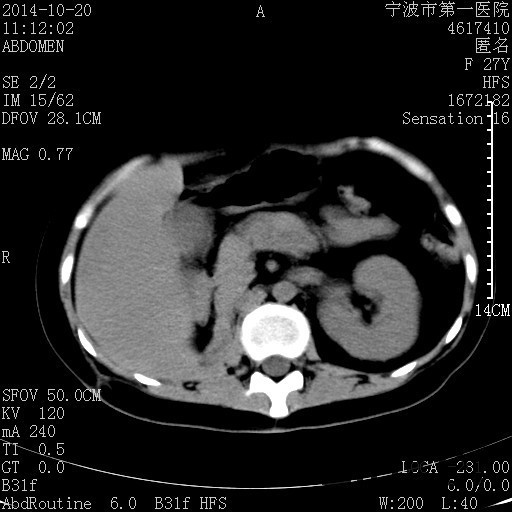

诊断为“气性肾盂肾炎,感染性休克,糖尿病酮症酸中毒” 血、尿、脓液培养均示“克雷伯杆菌” 入院第2天行“右双J管置入术” 入院第3天、7天行“右肾穿刺造瘘术” 入院1月行“右肾切除术” 术后顺利康复出院。

气性肾盂肾炎 • 气性肾盂肾炎是产气尿路病原体引起的急性肾实质坏死和肾周感染 • 大肠杆菌是最常见的病原菌,其次是克雷伯杆菌和变形杆菌 • 绝大多数气性肾盂肾炎患者合并糖尿病 • 死亡率19%至43%,单独的内科治疗通常是致命的,大部分患者最终需要行肾切除术 下一步治疗方案 • 拟行右肾切除术 • 患者经充分引流、抗感染治疗后现病情平稳,血糖控制良好 • 感染灶范围大,不能通过保守治疗消除,以往经验告诉我们保守治疗效果往往不佳 • 长期抗生素应用易引起真菌感染、伪膜性肠炎等并发症 • 若细菌对泰能耐药,后续抗感染治疗将十分困难 术前评估 • 手术风险评估(NNIS分级 2~3分) – IV 类手术切口(1分) – P3有严重系统性疾病,日常活动受限,但未丧失工作能力(1分) – T1手术在3小时内完成(0~1分) – 营养危险评分(NRS-2002) 营养状态评分3分+疾病严重程度评分2分=5分 围手术期治疗 • 术前、术中、术后血糖控制和调整 • 术后重症监护支持 • 感染控制和抗生素使用 • 手术前麻醉准备 患者最终在入院后1月行右肾切除术,术后康复出院。